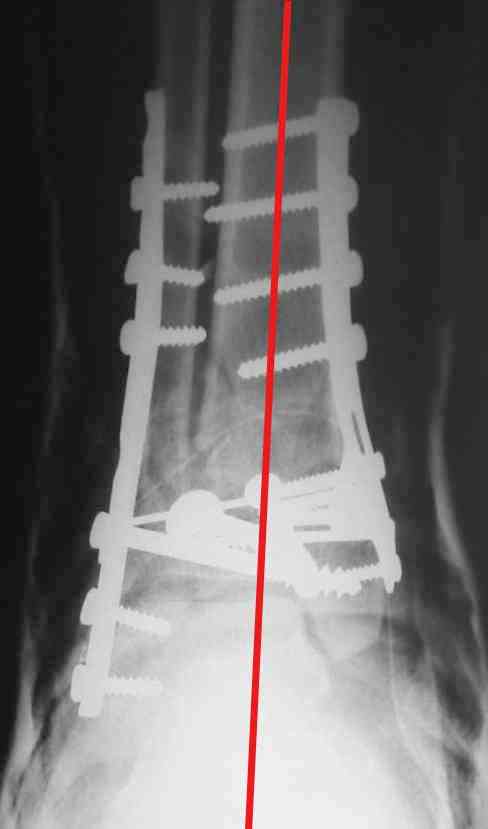

На представленном снимке видно, что эпифиз смещен латерально.

Сейчас с этим ничего не сделать, похоже.

Однозначно сказать сложно.Расстояние между тараном и медиальной лодыжкой меньше чем между тараном и крышей большеберцовой кости.Это может быть за счёт не правильной укладки.Пока не отчаиваетесь.Главное вы поняли принцип.Сделайте несколько проекций прямых и посмотрим.Для всех интересно.С уважением

В голеностопном суставе обязательны 3 стандартные ренгенологические проекции: прямая, латеральная и мортиз. Без них невозможно трактовать состояние голеностопа.